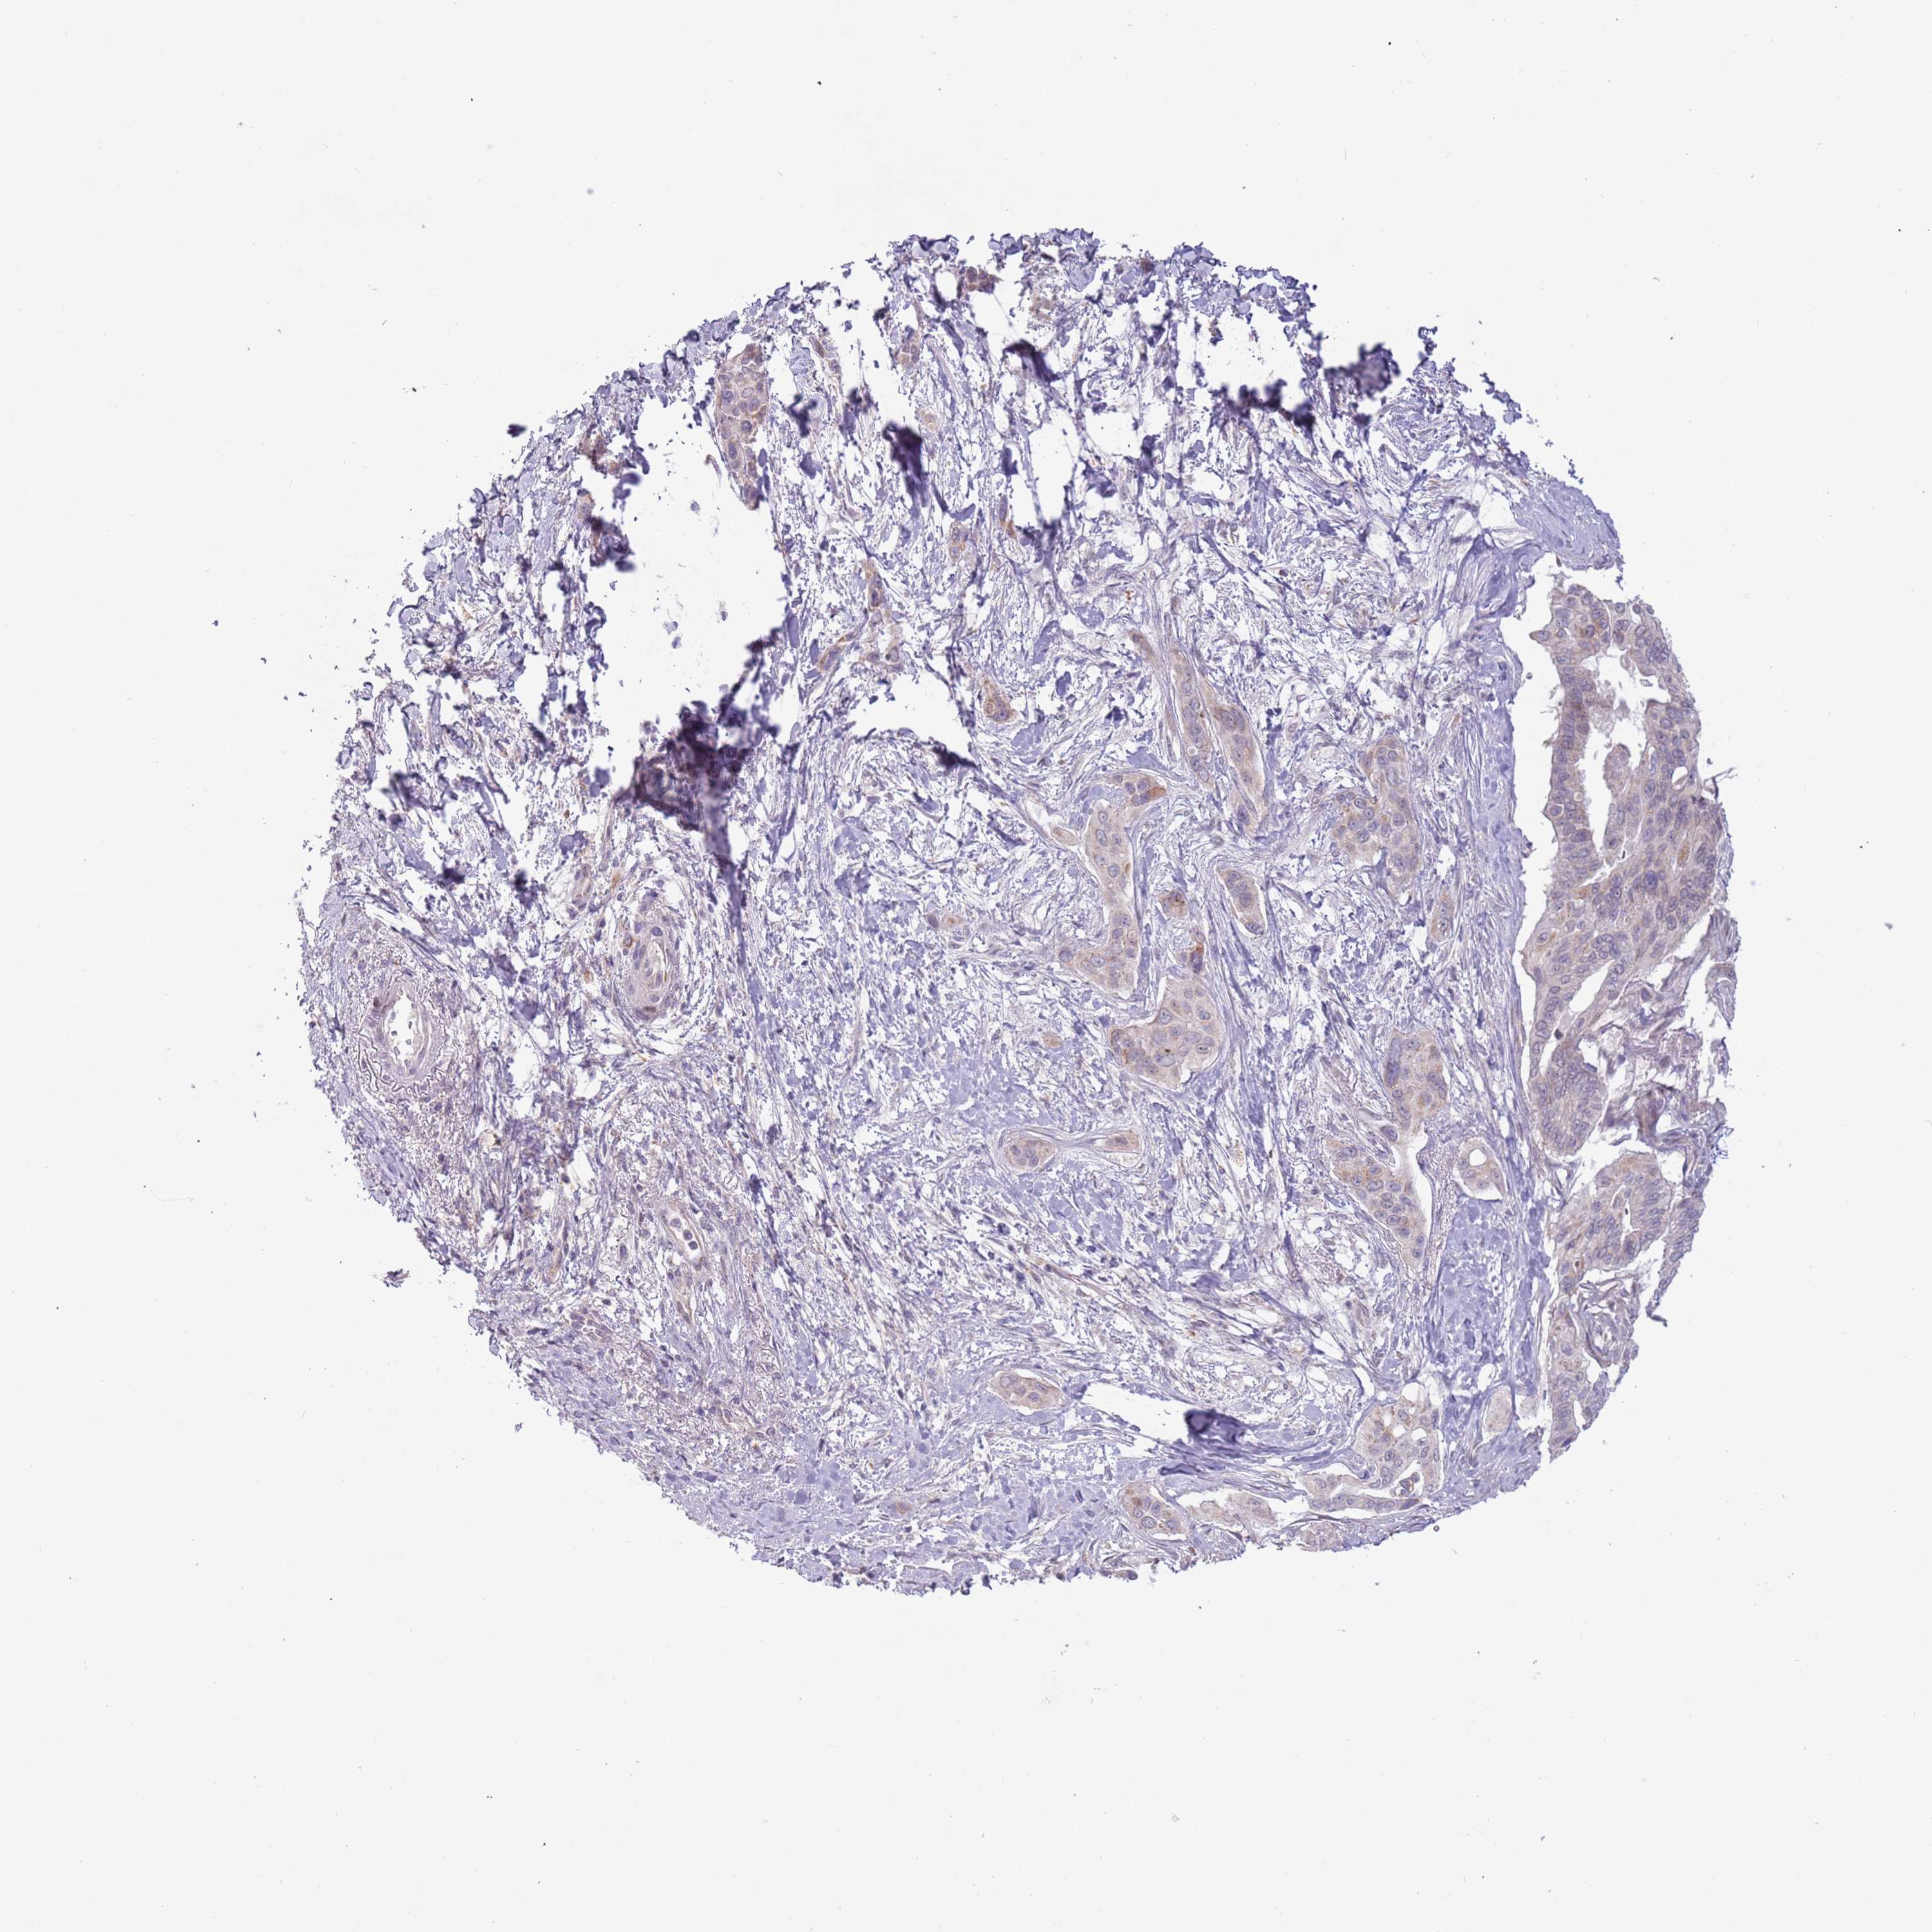

PANCREATIC CANCER - Protein expressioni

A mouse-over function shows sample information and annotation data. Click on an image to view it in a full screen mode. Samples can be filtered based on level of antibody staining by selecting one or several of the following categories: high, medium, low and not detected. The assay and annotation is described here.

Note that samples used for immunohistochemistry by the Human Protein Atlas do not correspond to samples in the TCGA dataset.

Antibody stainingi

Antibody staining in the annotated cell types in the current human tissue is reported as not detected, low, medium, or high, based on conventional immunohistochemistry profiling in selected tissues. This score is based on the combination of the staining intensity and fraction of stained cells.

Each image is clickable and will lead to virtual microscopy that enables deeper exploration of all samples and also displays staining intensity scores, fraction scores and subcellular localization as well as patient and tissue information for each sample.

Antibody HPA000540

Staining

High

Medium

Low

Not detected

Intensity

Strong

Moderate

Weak

Negative

Quantity

>75%

75%-25%

<25%

None

Location

Nuclear

Cytoplasmic/membranous

Cytoplasmic/membranous,nuclear

Adenocarcinoma, NOS